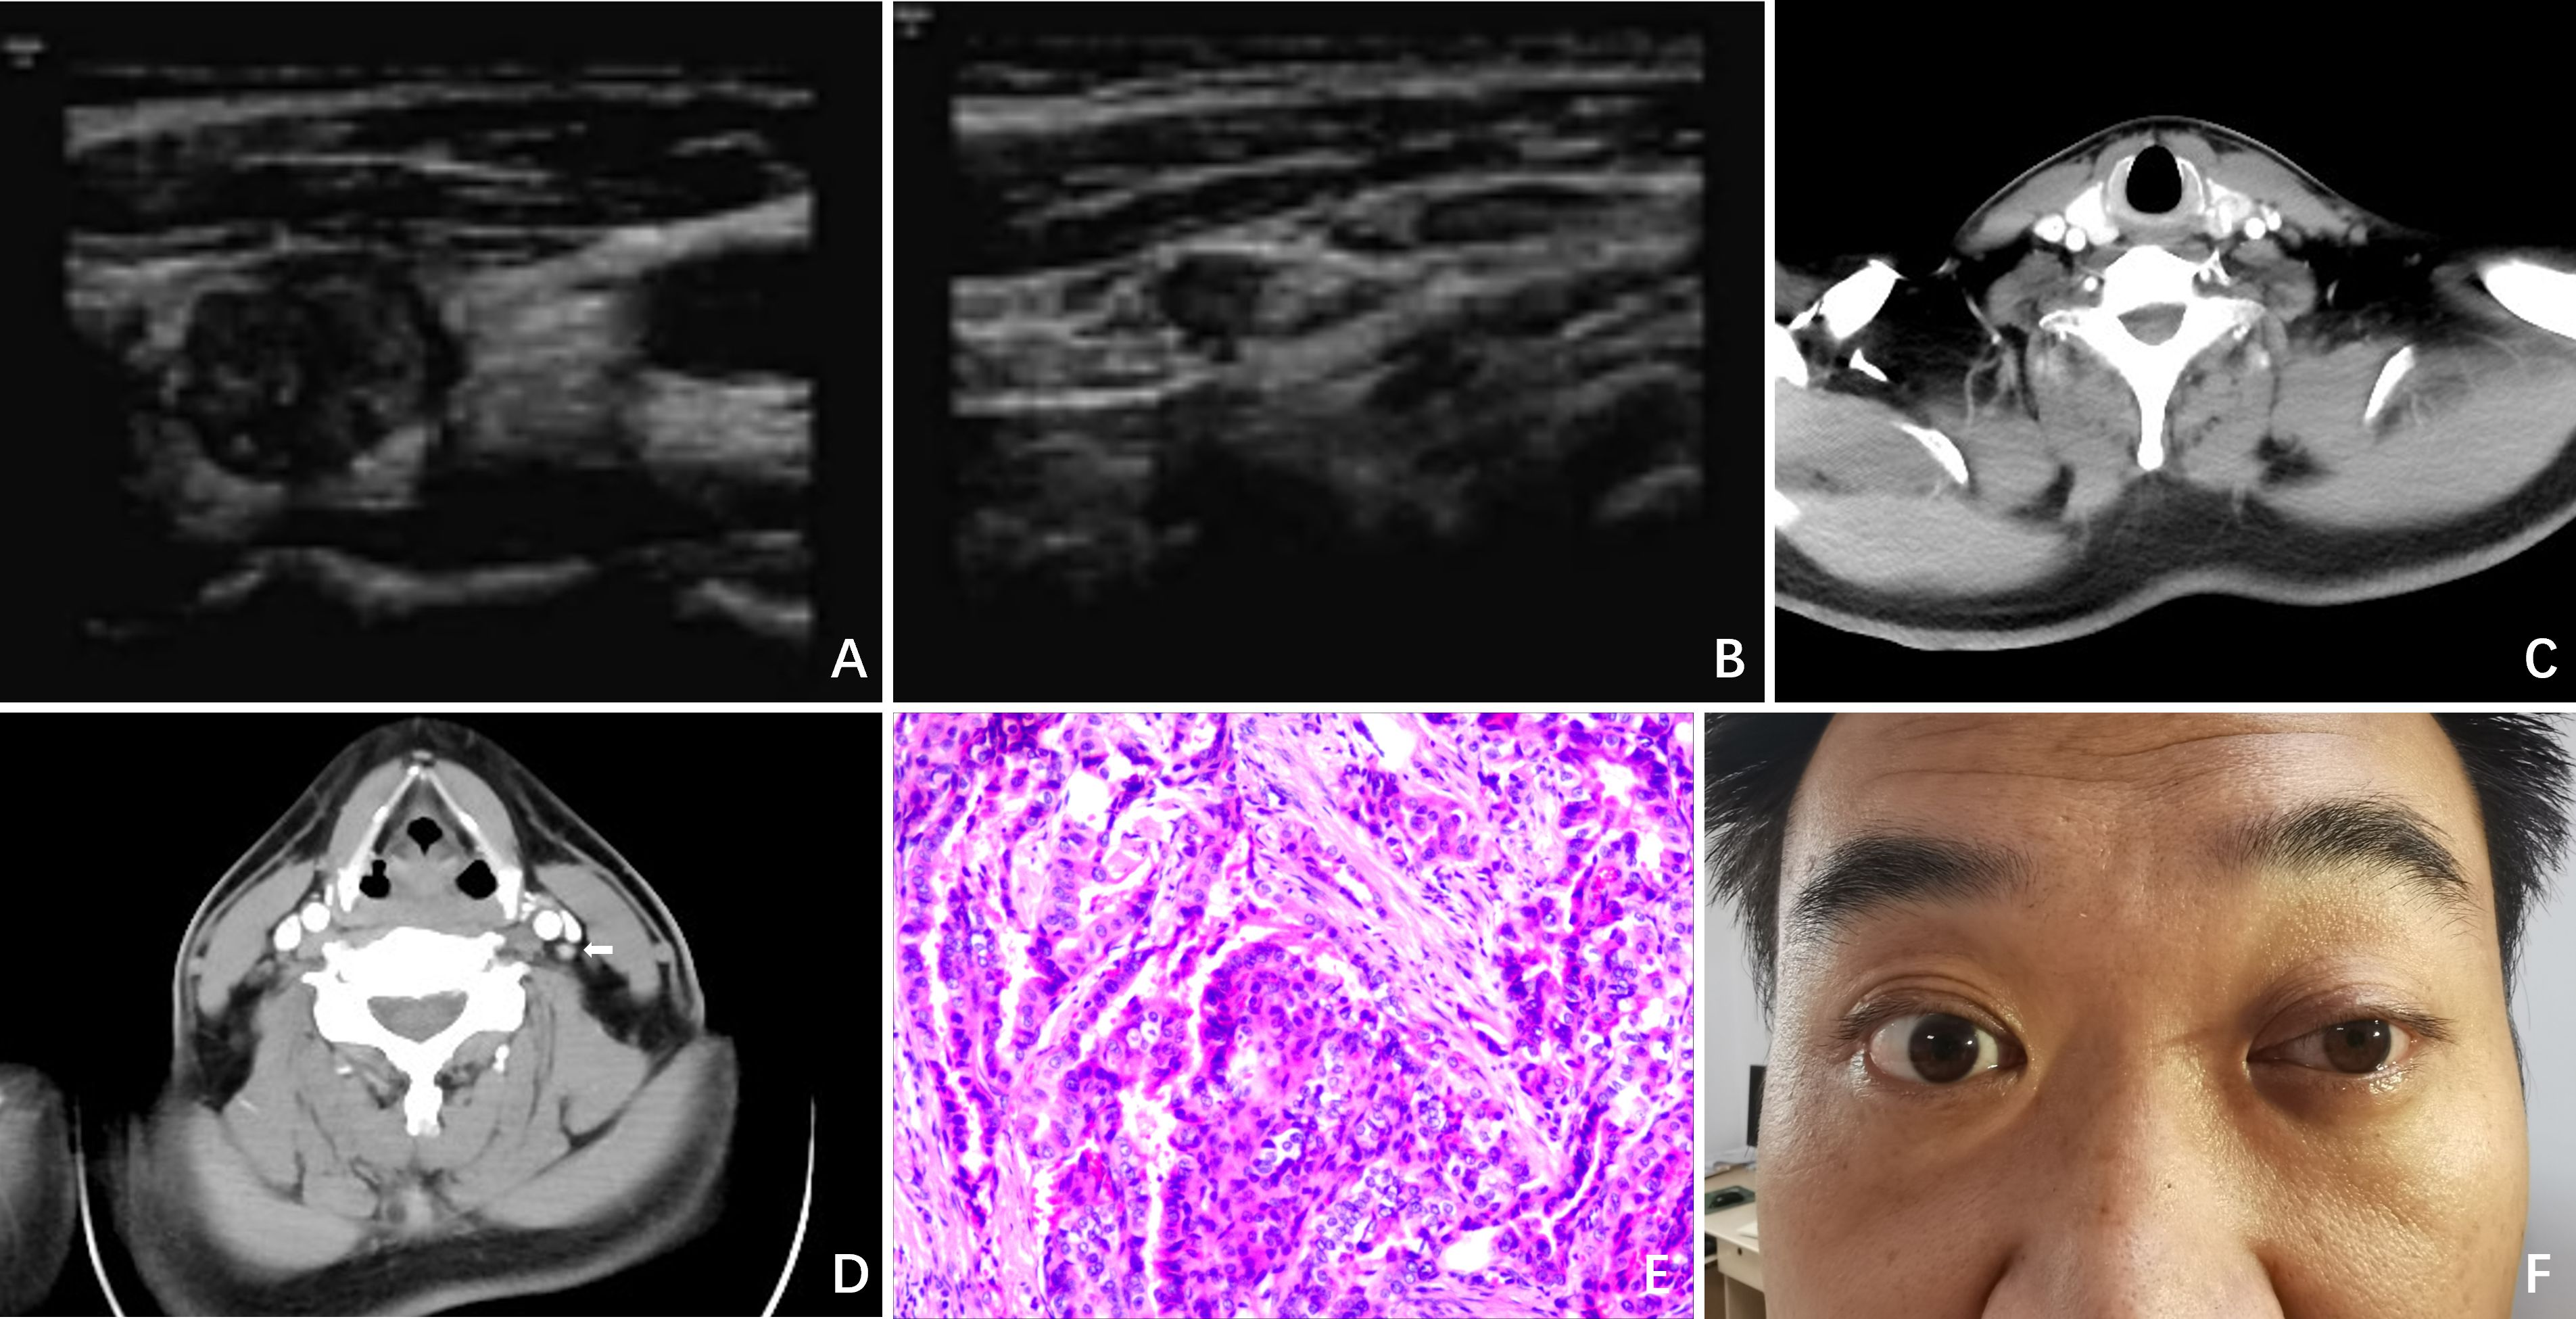

A 36 - year - old male underwent an ultrasound examination, during which a thyroid nodule was detected. The ultrasound revealed a nodule situated in the left lobe of the thyroid, measuring 1.4 cm x 1.4 cm x 1.6 cm, with low echogenicity and containing strong echo spots. The nodule was classified as TI - RADS 4a. Additionally, a 0.6 cm lymph node, also containing strong echo spots, was identified in the vicinity of level III of the left carotid artery sheath (Figures 1A, B). The patient denied having any clinical symptoms, a personal history, or a family history of thyroid disease. Upon physical examination, a firm nodule with a diameter of 2 cm was palpable in the left thyroid lobe. An enhanced computed tomography (CT) scan revealed a significantly enhanced nodule in the left lobe of the thyroid, along with a markedly enhanced lymph node at level III of the left neck, which was consistent with the lymph node findings assessed by ultrasound (Figures 1C, D). Subsequent fine-needle aspiration (FNA) biopsies of both the thyroid nodule and the lymph node confirmed the presence of papillary thyroid carcinoma (PTC) cells.

Figure 1. Clinical data. (A) Ultrasound revealed a nodule situated in the left lobe of the thyroid, measuring 1.4cm x 1.4cm x 1.6cm, with low echogenicity and containing strong echo spots; (B) Ultrasound revealed a 0.6cm lymph node containing strong echo spots in the vicinity of the left carotid artery sheath; (C) Enhanced CT revealed a significantly enhanced nodule in the left lobe of the thyroid; (D) Enhanced CT revealed a markedly enhanced lymph node at level II of the left neck (white arrow); (E) Postoperative pathology indicated PTC; (F) On POD 3, ptosis of the left eyelid, miosis, and anhidrosis on the ipsilateral face was observed in the patient.

The patient then underwent a total thyroidectomy (TT), accompanied by bilateral central lymph node dissection (CLND) and lateral lymph node dissection (LLND) that encompassed left levels II, III, IV, and V. Throughout the entire surgical procedure, we used an ultrasonic scalpel to incise the tissues while avoiding exposure of the CSC. Meanwhile, intraoperative nerve monitoring (IONM) was employed to ensure the normal transmission of signals from the recurrent laryngeal nerve and vagus nerve. Stimulation of the phrenic nerve and accessory nerve resulted in the expected muscle movements, confirming their functionality. The operation proceeded smoothly without any complications or unexpected findings. Postoperative pathological examination further confirmed the diagnosis of PTC (Figure 1E). The status of lymph node metastasis is as follows: right level VI (0/4), left level II (0/4), level III (3/18), level IV (2/9), level V (0/2), and level VI (4/6).

On postoperative day (POD) 3, we observed ptosis of the left eyelid, miosis, and anhidrosis on the ipsilateral face, with no signs of vascular dilatation (Figure 1F). Consequently, a thorough ocular examination was conducted collaboratively by a neurologist and an ophthalmologist. After excluding other potential complications such as hematoma, dyspnea, inflammation, or vocal cord issues, the patient was diagnosed with HS.